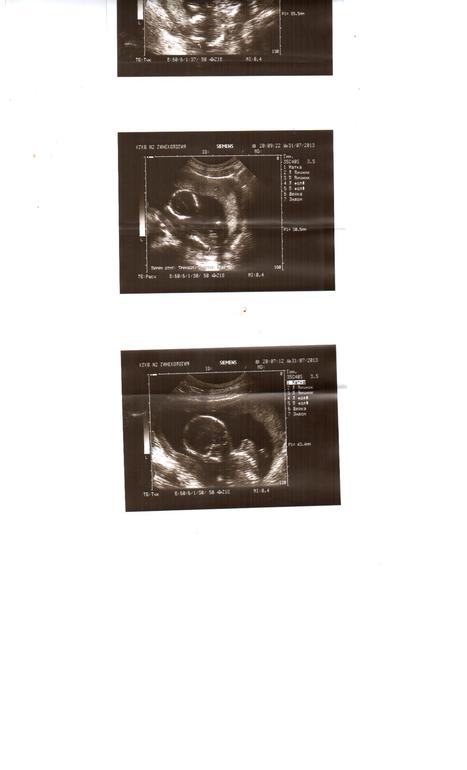

решила и я выложить фоточку узи)) с 18 недельки

жаль пола не видно

все анализы на патологии в норме)) на узи сказали что мой пупс развивается нормально))

пол нам не захотел показать сидел бочком и ножки прижал)))

муж в диком восторге он со мной в первый раз на узи пошел))

у них так сказать первое знакомство было))